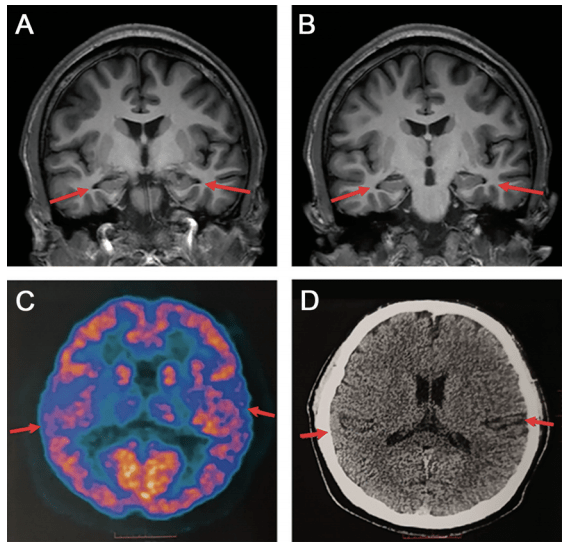

海马硬化的影像诊断

影像学检查:患者脑 mri 显示双侧海马体轻度萎缩,脑沟和脑裂轻度增宽.